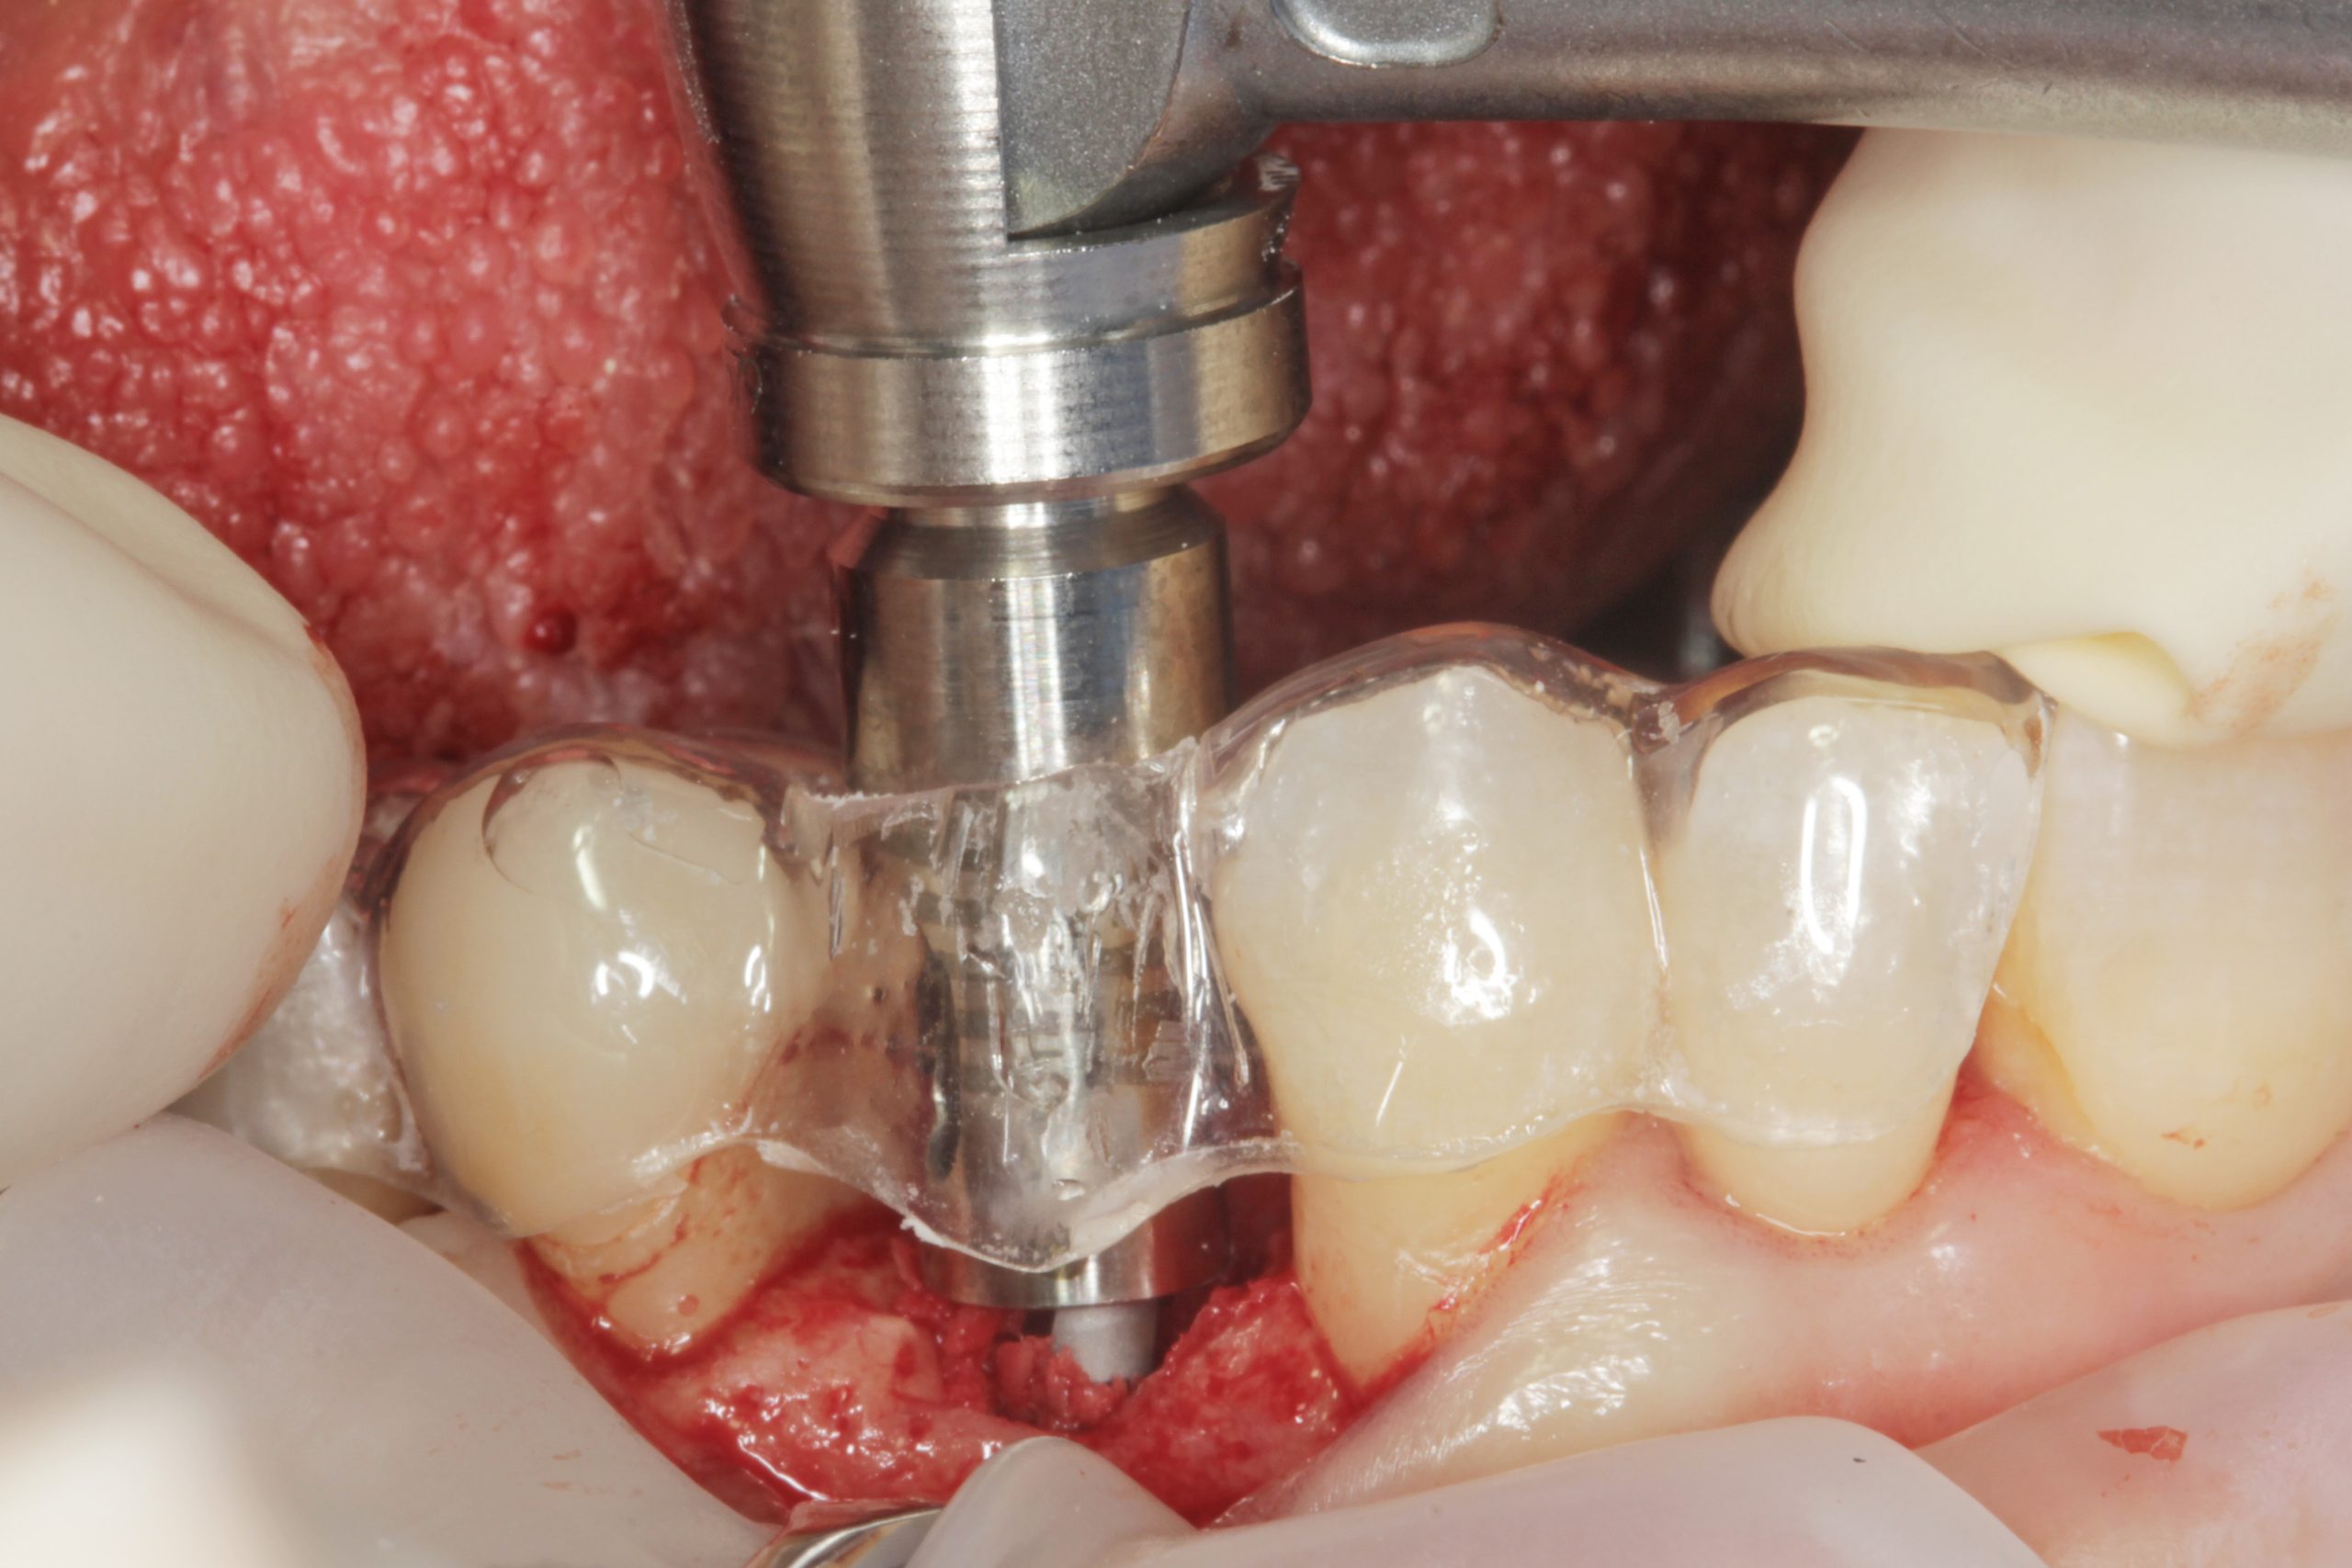

L’integrazione di queste migliorie con la chirurgia guidata ha portato ulteriori benefici, specialmente nei casi in cui il preciso posizionamento di un impianto diventa fondamentale a causa delle limitazioni anatomiche o spaziali presenti e della riabilitazione protesicamente guidata desiderata. Il nostro gruppo ha sviluppato un nuovo sistema di chirurgia guidata, chiamato Stop & Guide® (BTI Biotechnology Institute), capace di superare il modello tradizionale fresa e boccola. Questo protocollo utilizza driver statici non rotazionali come elementi di orientamento durante l’osteotomia, così da controllare l’angolazione, la profondità e il livello dell’impianto (iuxtacrestale, subcrestale o sovracrestale) durante il suo posizionamento.

Il vantaggio principale risiede nel fatto che il clinico ha la possibilità di utilizzare il protocollo di fresaggio convenzionale che utilizza di solito con minimi cambiamenti. Aggiunge infatti solo i driver. Tra i benefici sono inclusi un minor numero di componenti, una maggior versatilità, assenza di frizione tra la fresa e la guida, maggiori semplicità e controllo durante tutto il corso della procedura. L’utilizzo combinato di impianti Core-X® e Stop & Guide® porta in sé due fattori chiave: aumenta la stabilità primaria biomeccanica e migliora la precisione nel posizionamento, fattori che non possono che garantire maggiori predicibilità e semplificazione del trattamento, anche e soprattutto nei casi più complessi. Nella serie di casi che qui presentiamo nei quali è stato utilizzato questo protocollo (impianti Core-X® posizionati con Stop & Guide®).

La pianificazione preoperatoria virtuale ha incluso la scansione intraorale e la CBCT. Con i dati raccolti sono stati generati modelli virtuali altamente precisi dell’anatomia del paziente ed è stata pianificata la posizione ideale degli impianti. In base a questa pianificazione sono state prodotte dime chirurgiche CAD/CAM per replicare la posizione e l’angolazione implantare pianificate. Le dime sono state fatte calzare sui denti adiacenti, incorporando i driver statici coerenti con il manipolo chirurgico utilizzato dall’operatore (Figura 1).

Grazie a dima e drivers, la chirurgia guidata consente una fresatura biologicamente incrementale come con un protocollo convenzionale; l’osso autologo raccolto durante la fresatura può essere utilizzato come particolato da innesto al bisogno. I dati clinici e demografici raccolti includono età, sesso, storia clinica e terapie farmacologiche in atto. I dati correlati agli impianti includono, invece, localizzazione anatomica, diametro, lunghezza, torque di inserzione, tipo di protesi, e parametri ossei rilevati alla diagnosi (Figure 2-3). Nel corso del follow-up sono stati registrati la sopravvivenza implantare protesica e il livello di osso marginale. I dati sono stati registrati da un esaminatore indipendente.